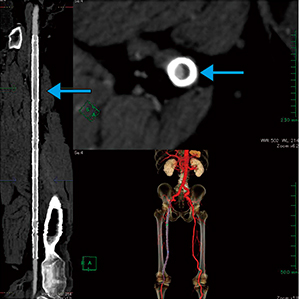

CPR表示機能は,3つのMPR画像から最適な画像で点をとり,中心線推定やスラブ厚調整などを行うだけで彎曲部分を平面的に,またストレート表示でも観察でき,プラークや石灰化などの狭窄箇所をわかりやすく観察することができる。

ASO(閉塞性動脈硬化症)治療後のステント内狭窄における血流形態・狭窄評価(図8)と,脊柱側彎症の手術前検査におけるO-armシミュレーション用の形態評価・血管走行確認(図9)の画像を示す。

図8 ASO治療後の狭窄評価 |